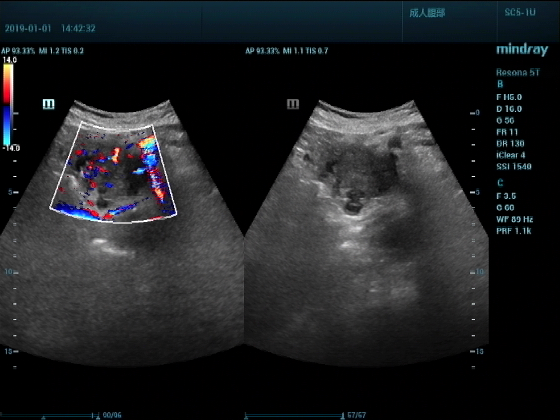

超声入门贴959--胰头癌并胰管扩张

男,88岁,腹部隐疼2个月加重3天来诊